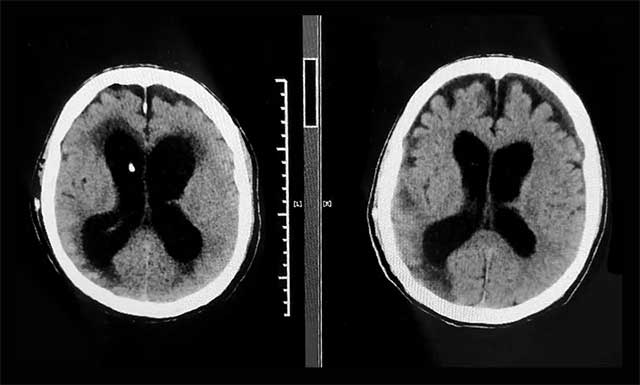

▲ 术前(左)和出院前(右)CT比对,患者原先扩张的脑室已缩小,症状改善明显

入院时,汪先生神志昏迷、气管切开无法自主呼吸、鼻饲饮食、留置尿管,可以说处于“植物人”状态。像这样的脑出血昏迷患者,病情随时可能恶化,张琪博士团队为患者完善相关检查,结合既往病史,多次开展病情讨论评估,制定了有针对性的治疗方案。鉴于患者有中度脑积水,严重影响意识恢复,张琪博士亲自为患者进行了脑室-腹腔分流手术。

手术非常顺利,汪先生的意识也逐渐恢复。